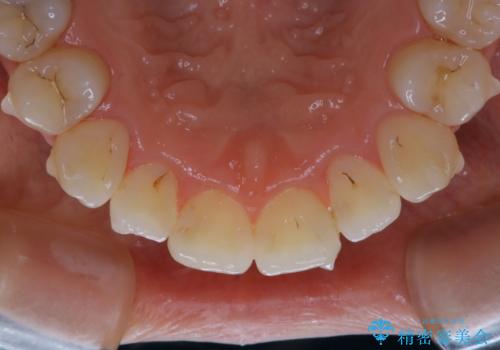

- インビザラインでの矯正治療中ですが、結婚式があるため全体の着色・ステインを綺麗にしたいとのことでした。PMTC60分コースを行いました。

PMTC(保険外治療)は、毎日の歯磨きで落としきれない汚れや、コーヒ、紅茶・タバコのヤニなどの着色も除去します。目には見えない歯と歯の間・歯肉の境目・インビザライン中はアタッチメント周囲などに残っているプラーク(歯垢)もしっかり取り除きます。PMTCでは専門的な機械や材料を使用して、徹底的に汚れを除去するため、虫歯・歯周病・口臭予防などにつながります。

またPMTCを行うことで、ご自身本来の歯の色になり自然な明るさになります。

口元が自然な明るさになることで、より清潔感のある印象になるため結婚式・行事やイベント前などにもPMTCを行うはおすすめです。